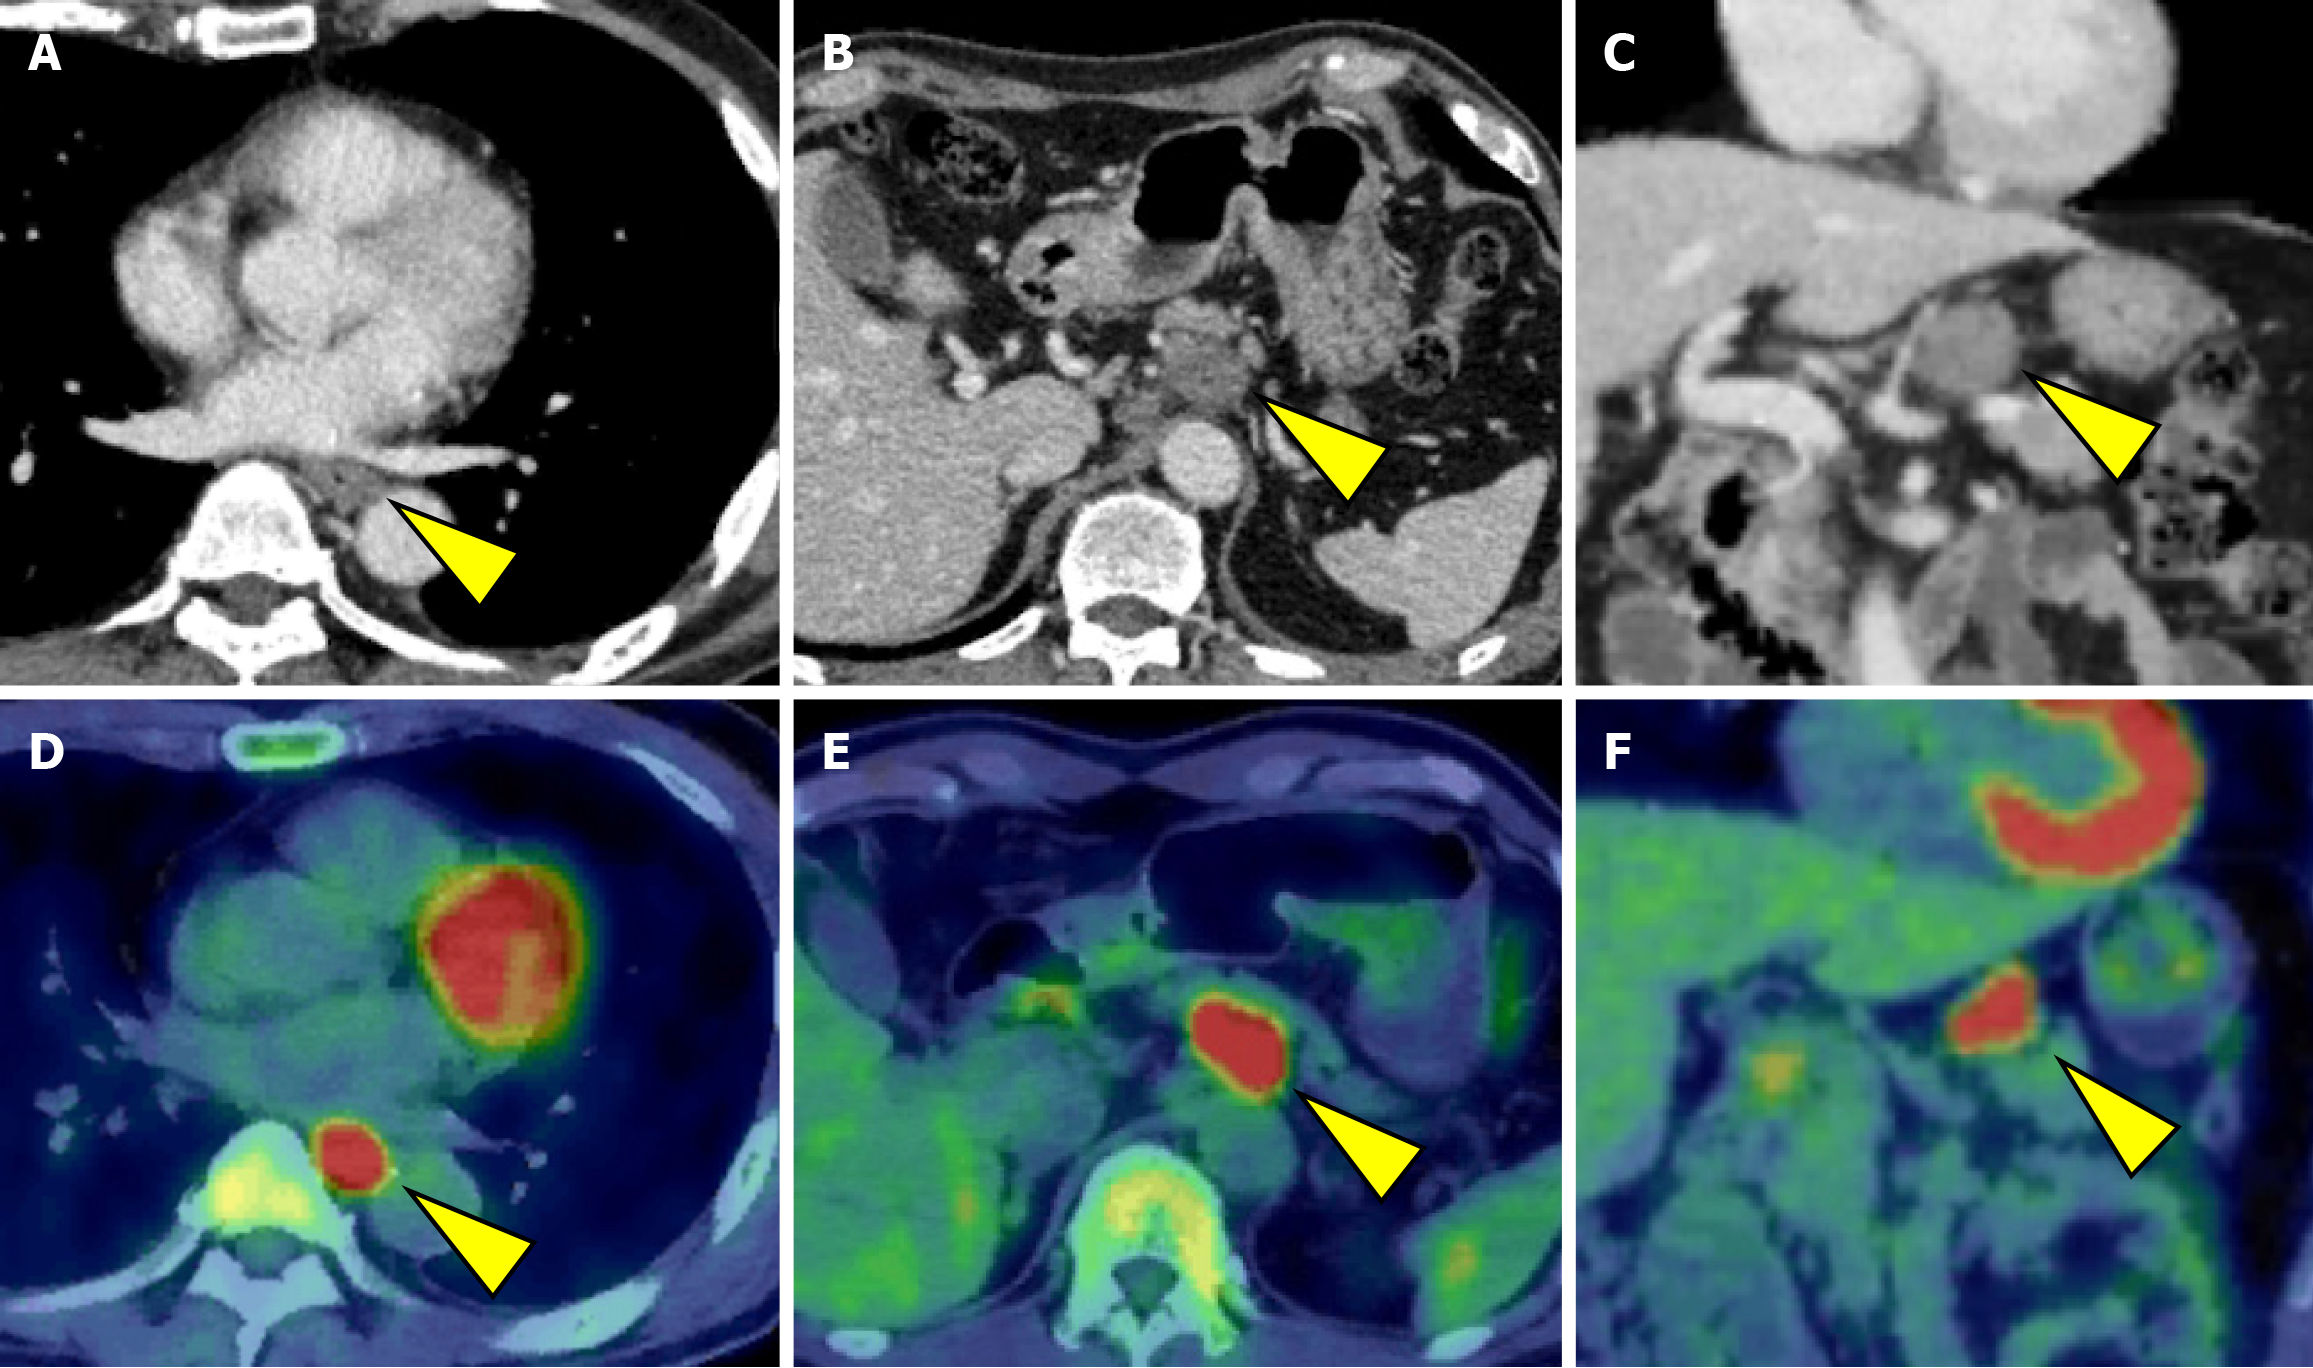

Initially, we planned to administer chemotherapy, and conversion surgery would be considered if the tumor became resectable following the chemotherapy. The induction chemotherapy involved docetaxel + cisplatin + 5-fluorouracil (DCF) (docetaxel 70 mg/m2/day on day 1, cisplatin 70 mg/m2/day on day 1, and 5-fluorouracil 750 mg/m2/day on days 1-5). After three courses of DCF chemotherapy, EGD and CT revealed shrinkage of the primary lesion (Figures 1B and 3A). Additionally, CT demonstrated a remarkable reduction in the size of the metastases involving No. 101L, No. 8, and No. 9. In contrast, the No. 11p lymph node showed only slight shrinkage (Figure 3B and C). Positron emission tomo